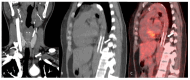

Systemic vasculitides are a rare and complex group of diseases that can affect multiple organ systems. Clinically, presentation may be vague and non-specific and as such, diagnosis and subsequent management are challenging. These entities are typically classified by the size of vessel involved, including large-vessel vasculitis (giant cell arteritis, Takayasu's arteritis, and clinically isolated aortitis), medium-vessel vasculitis (including polyarteritis nodosa and Kawasaki disease), and small-vessel vasculitis (granulomatosis with polyangiitis and eosinophilic granulomatosis with polyangiitis). There are also other systemic vasculitides that do not fit in to these categories, such as Behcet's disease, Cogan syndrome, and IgG4-related disease. Advances in medical imaging modalities have revolutionized the approach to diagnosis of these diseases. Specifically, color Doppler ultrasound, computed tomography and angiography, magnetic resonance imaging, positron emission tomography, or invasive catheterization as indicated have become fundamental in the work up of any patient with suspected systemic or localized vasculitis. This review presents the key diagnostic imaging modalities and their clinical utility in the evaluation of systemic vasculitis.